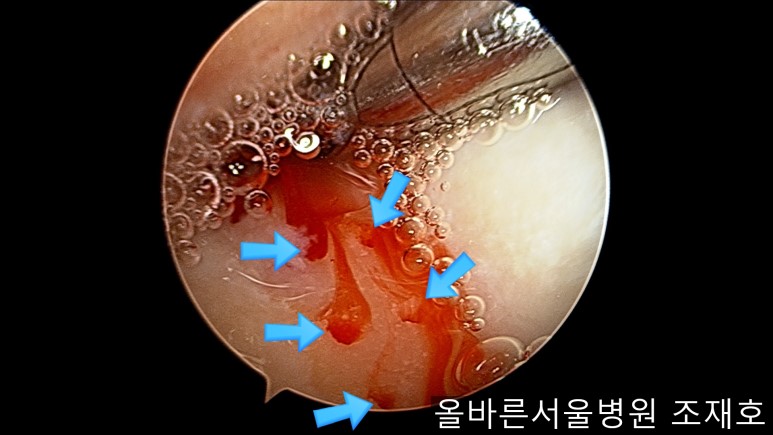

通过关节镜图像可看到:由于内侧股骨髁软骨损伤骨头已经显露出来。

胫骨上端的软骨损伤严重,也露出了骨头。

正是缺失软骨的部位碰到一起,引发剧烈疼痛,腿部逐渐变形。

为了软骨再生,在胫骨上端进行微骨折术。

胫骨上端是通过微骨折术,可再生软骨的地方。

尽量将孔打地细密,确认此处骨髓腔内的血流出。

在股骨部位用CARTISTEM注射用4mm激光钻细密打孔,并确保软骨板不倒塌。不用切开通过关节镜即可完成手术。

如图,尽量细密打孔。